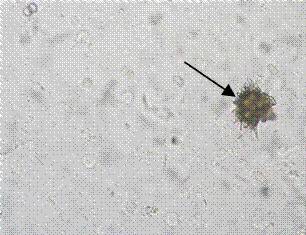

3、箭头所指细胞内结构的名称:颗粒管型 蜡样管型